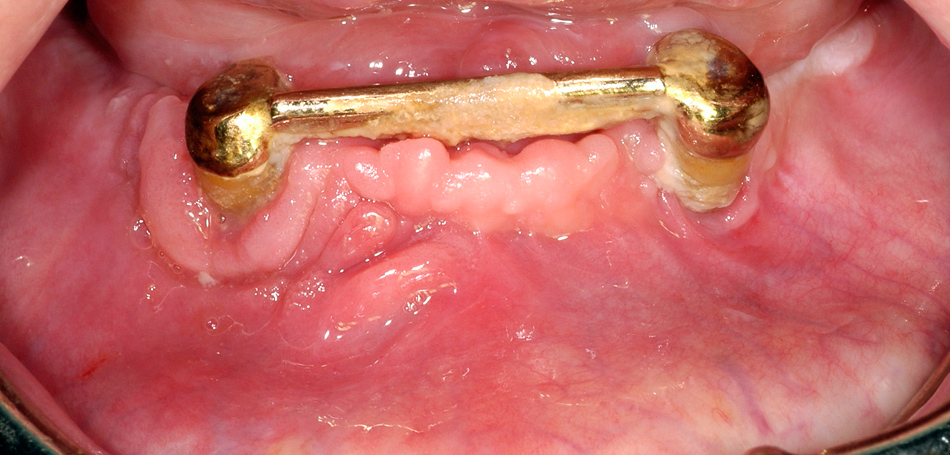

In addition to systemic and general factors, some local events are clearly linked to the occurrence of osteopathology. Similar to our 2006 study [1], each patient in our present sample had a local event in the same area as subsequent bone necrosis. Most (64%) patients had previous dental extractions, but periodontal disease, pressure ulcers, root canal treatment, implant insertion, and periapical infections were also evaluated as local risk factors. Dental extractions were clearly shown to increase the risk of ONJ development. Vahtsevanos et al. [19] reported an 18–33-fold higher risk of ONJ development in patients with a dental extraction history, and other authors have confirmed this finding. In the same study, Vahtsevanos et al. [19] reported a two-fold higher risk in patients wearing dentures, supposedly due to the direct negative influence of BP on mucosal healing. Implant insertion remains under discussion as a local risk factor, especially in patients with osteoporosis. To date, few reports have described patients with BRONJ in association with dental implant placement. Lazarovici et al. [27] for example, presented a case series in which implant insertion was a local triggering factor in 27/145 (18.6%) patients with BRONJ, regardless of whether the patients had a malignant disease or osteoporosis. In this study, dental implant insertion was a local triggering factor for the development of subsequent osteopathology in 15 (14%) patients. According to other studies [28], not only implant insertion, but also peri-implant communication between the implant and the jawbone seems to be a risk factor [29]. Several studies or case series have shown that ONJ in areas of previously inserted implants developed chronologically independently from the insertion procedure [28, 30].